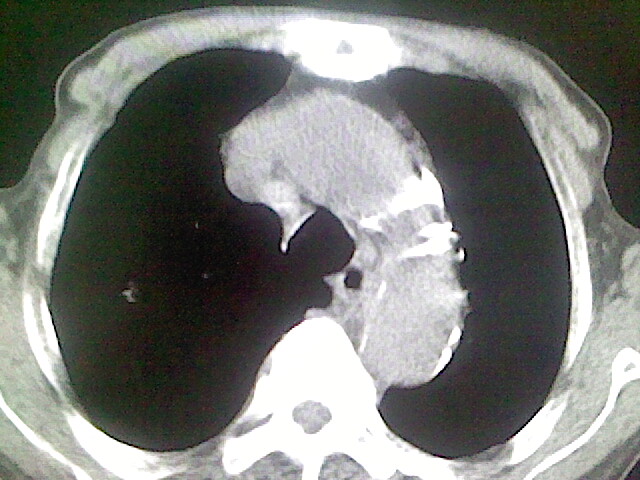

以下是引用zsl6918在2008-8-28 16:49:00的发言:[br]双肺炎性病灶,食管狭窄估计与心房增大压迫所致。

以下是引用xulianj在2008-8-28 20:36:00的发言:[br]慢支肺气肿伴感染,右上肺陈旧性结核;食道建议胃镜检查。

以下是引用wqs571018在2008-8-28 21:18:00的发言:[br]慢支继发感染,右上肺陈旧性结核;食道建议胃镜检查。